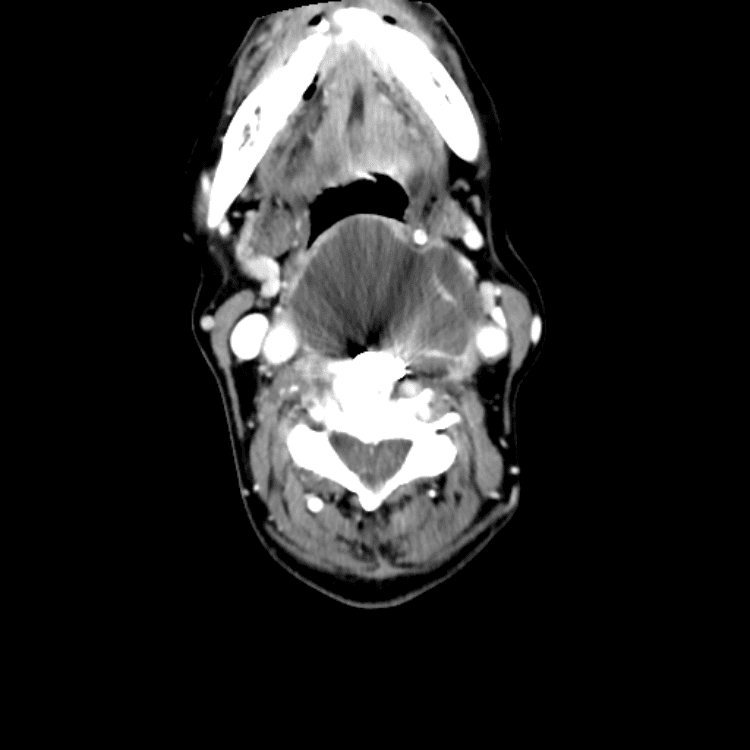

Head and Neck

Practice

Simulates call by including subtle or difficult cases and some normals.

27 cases